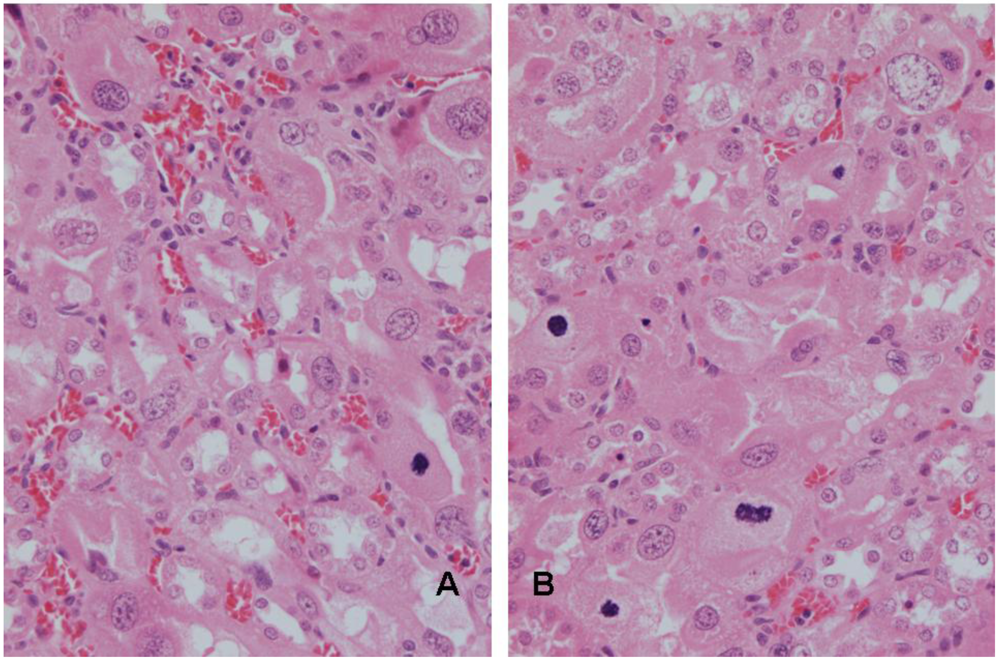

A,B. Renal histopathology of rat 5 after 10 weeks exposure to P. polonicum-contaminated diet, showing karyomegalic nuclei with prominent nucleoli in extensively distorted epithelium of P3 segments of nephrons. Mitoses, indicated by the condensed chromatin, reflect current mitogenic influence of the mycotoxin. Some cells have several nuclei.

In rat 4, after five weeks on the P. polonicum-contaminated diet, the karyomegaly seen clearly in rats 1–3 above after four days had progressed in magnitude and frequency to the striking karyocytomegaly illustrated in Figure 1. After ten weeks treatment for rat 5, unilateral nephrectomy provided tissue for histology showing further progression of karyocytomegaly while mitotic events continued (Figure 2 A, B). Monitoring body weight in rat 5 (Figure 3) showed that P. polonicum was well tolerated for a total of 463 days since first exposure. Permanent transfer then to normal feed coincided with foot lesions caused by maintaining a heavy animal on paper, reflected in the temporary decline in body weight (Figure 3) while lesions healed. Notably, fertility was confirmed 693 days after P. polonicum exposure commenced (25 months of age); five weeks later the rat was found moribund and euthanized. The only notable feature at necropsy was the remaining kidney (9.4 g, 3.3 cm long axis), much enlarged at least to compensate for the previous unilateral nephrectomy. The kidney surface implied extensive cysts, which are commonly a feature of ageing. Histology revealed the cysts, and persistent karyocytomegaly in the cortico-medullary region, but there was no evidence of tumour.